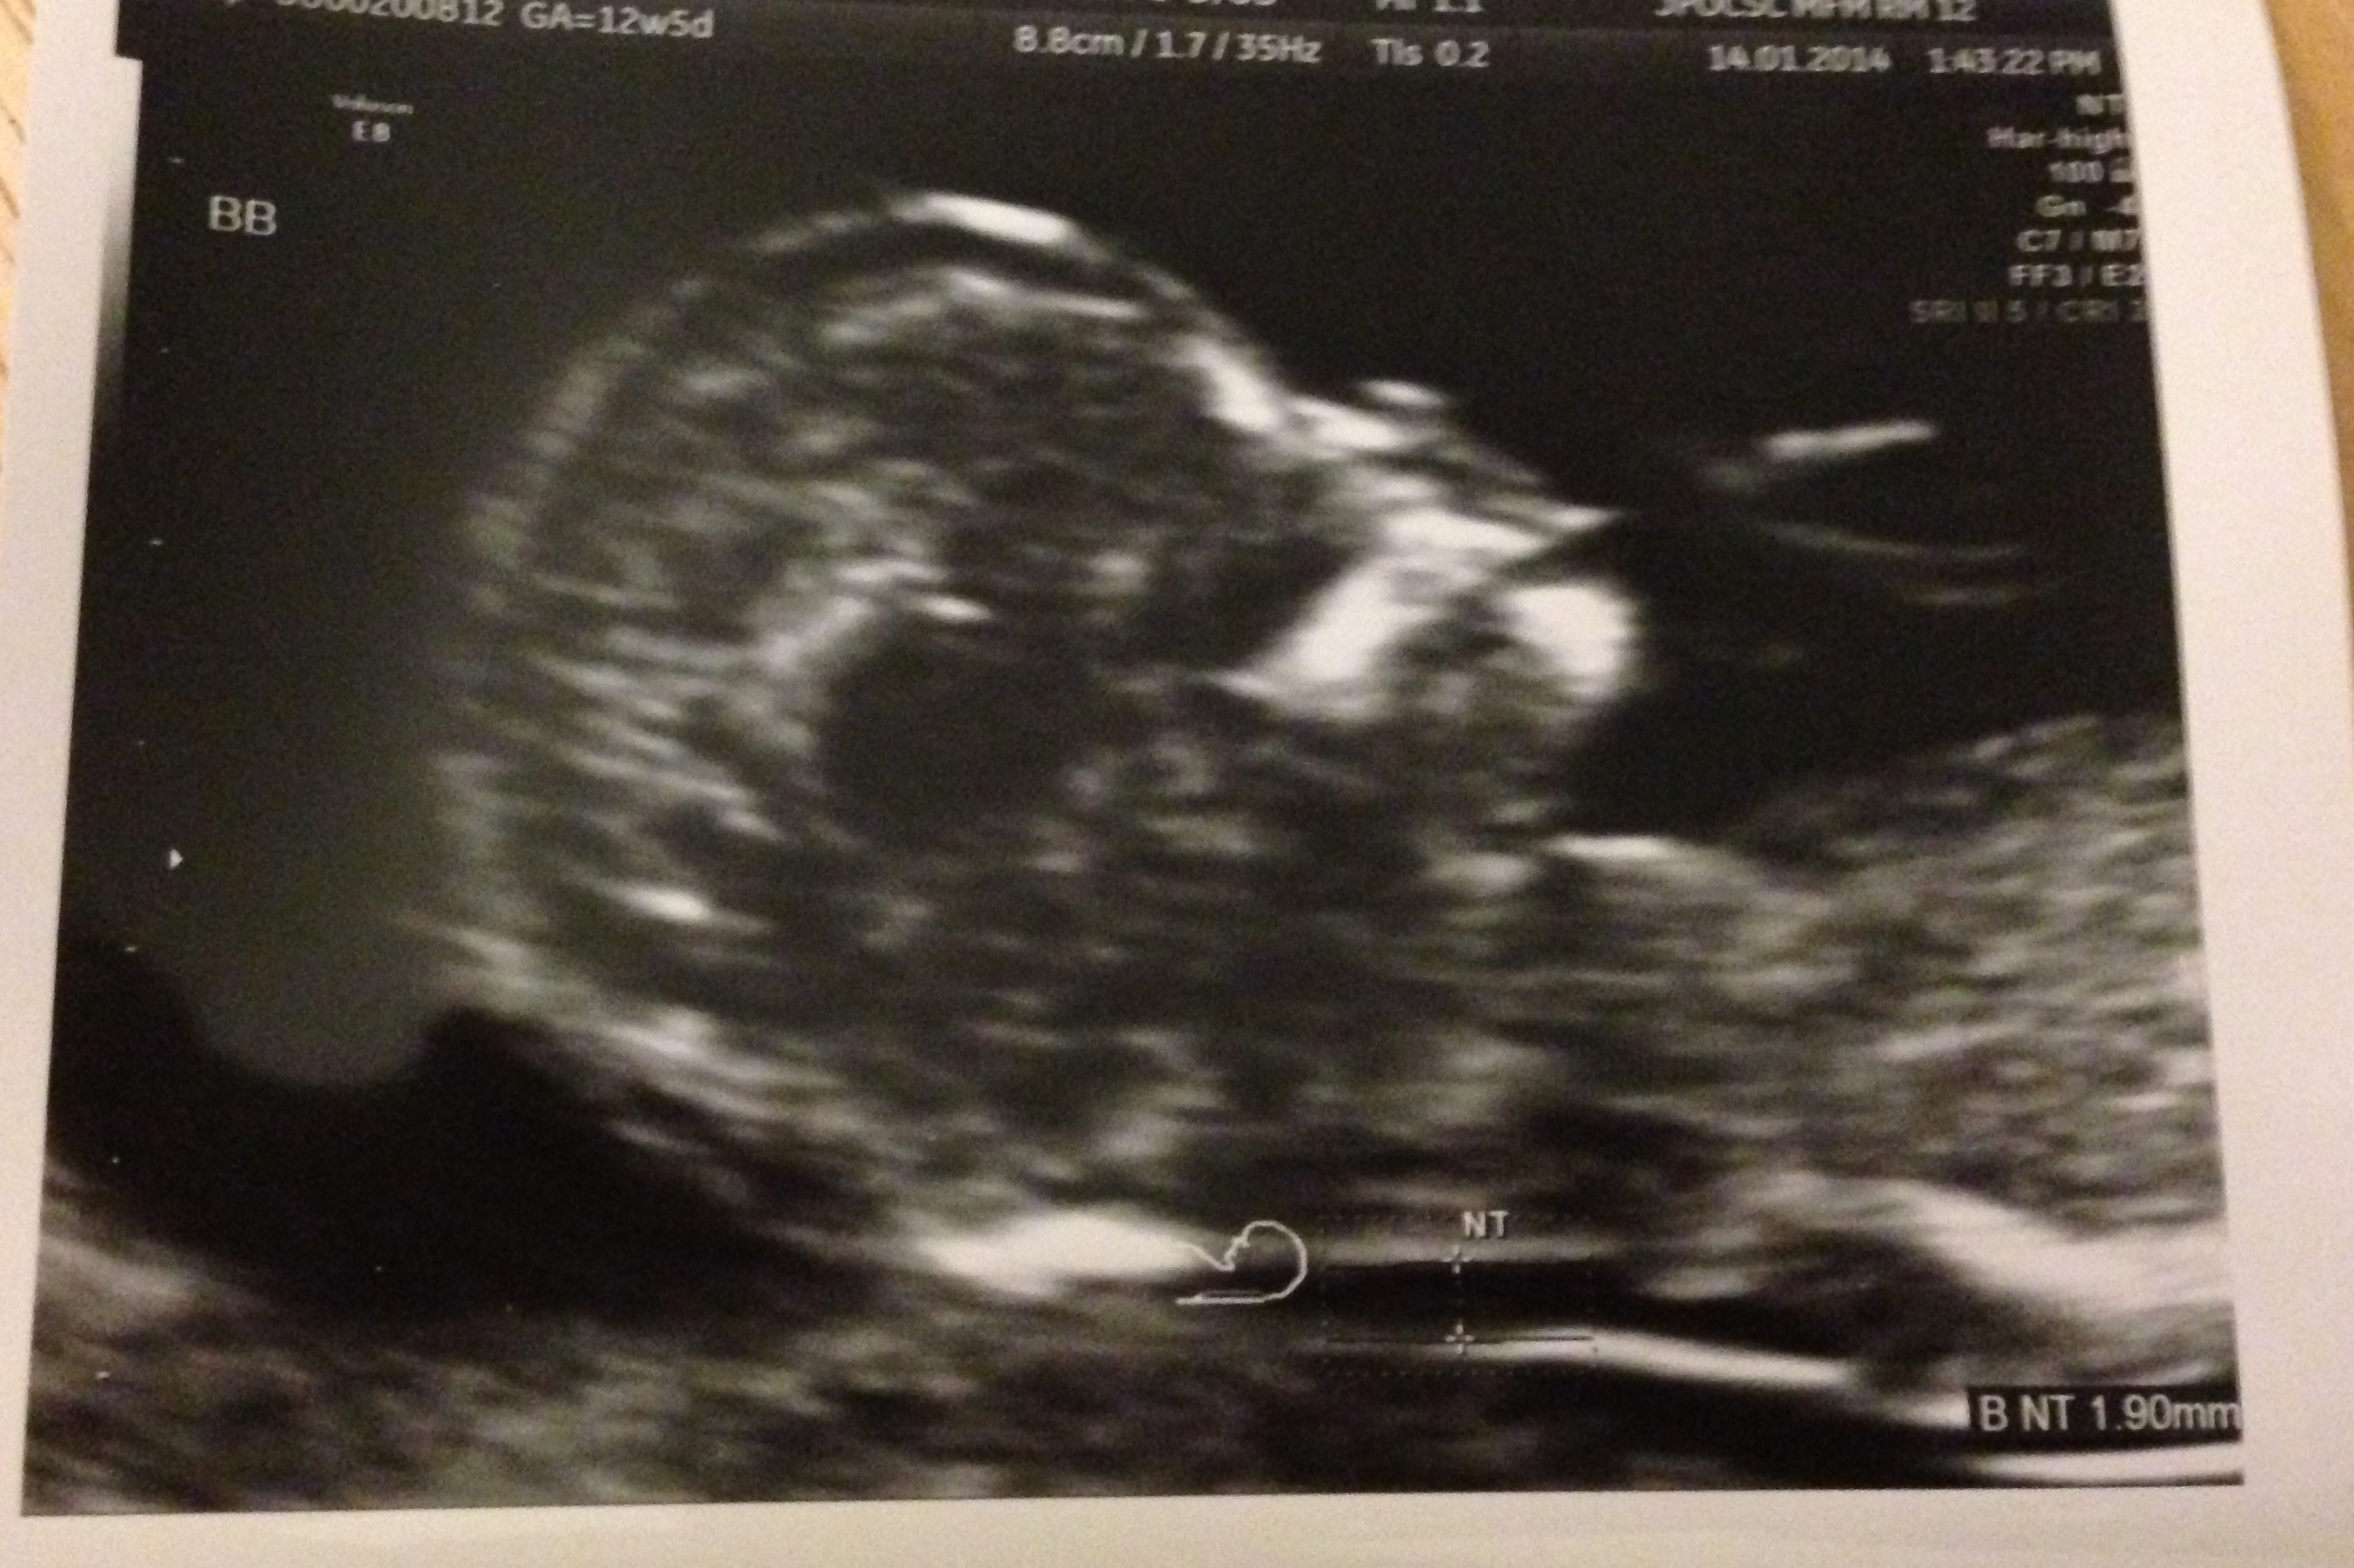

Today I met with my MFM for the first time and ended up getting an NT scan out of it! Both babies looked great and they were wiggling around a bunch, was very cute.  He did tell me b/c they're di/di I don't need to keep seeing him in conjunction with my OB. I'm still high risk, but the lowest of the high risk I guess. I was a bit upset at first, but I assume he knows what he's doing. I also get to go for an early GD screening this week, so I have that to look forward to.

Anyways, just wanted to share. I'd been looking forward to this appointment since I got it. And here's pictures of the little babies (and yes, that's A's hand at his/her mouth). And thanks for all the support the other day in regards to the MFM questions. It was so helpful!